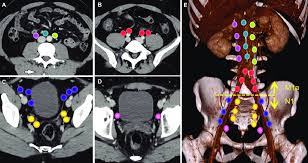

Pathways Of Lymphatic Spread In Male Urogenital Pelvic Malignancies Radiographics from pubs.rsna.org Usually they are detected either by modern imaging techniques or by the histological analysis of the lymph nodes themselves, when removed prophylactically during a surgery. Prostate cancer metastasis occurs when cells break away from the tumor in the prostate. Lymph node metastases in prostate cancer. The m in the tnm system indicates whether the prostate cancer has spread to other parts of the body, such as the lungs or the bones. Lymph nodes are found throughout the body including in the pelvic area, near the prostate. Prostate cancer that spreads to lymph nodes has the highest survival rate meanwhile, lung and bone are 'somewhere in the middle,' study said the findings could help guide treatments for advanced. The n (nodes) score rates whether the cancer has spread into nearby lymph nodes. A lymph node biopsy may be done if the doctor thinks the cancer might have spread from the prostate to nearby lymph nodes.